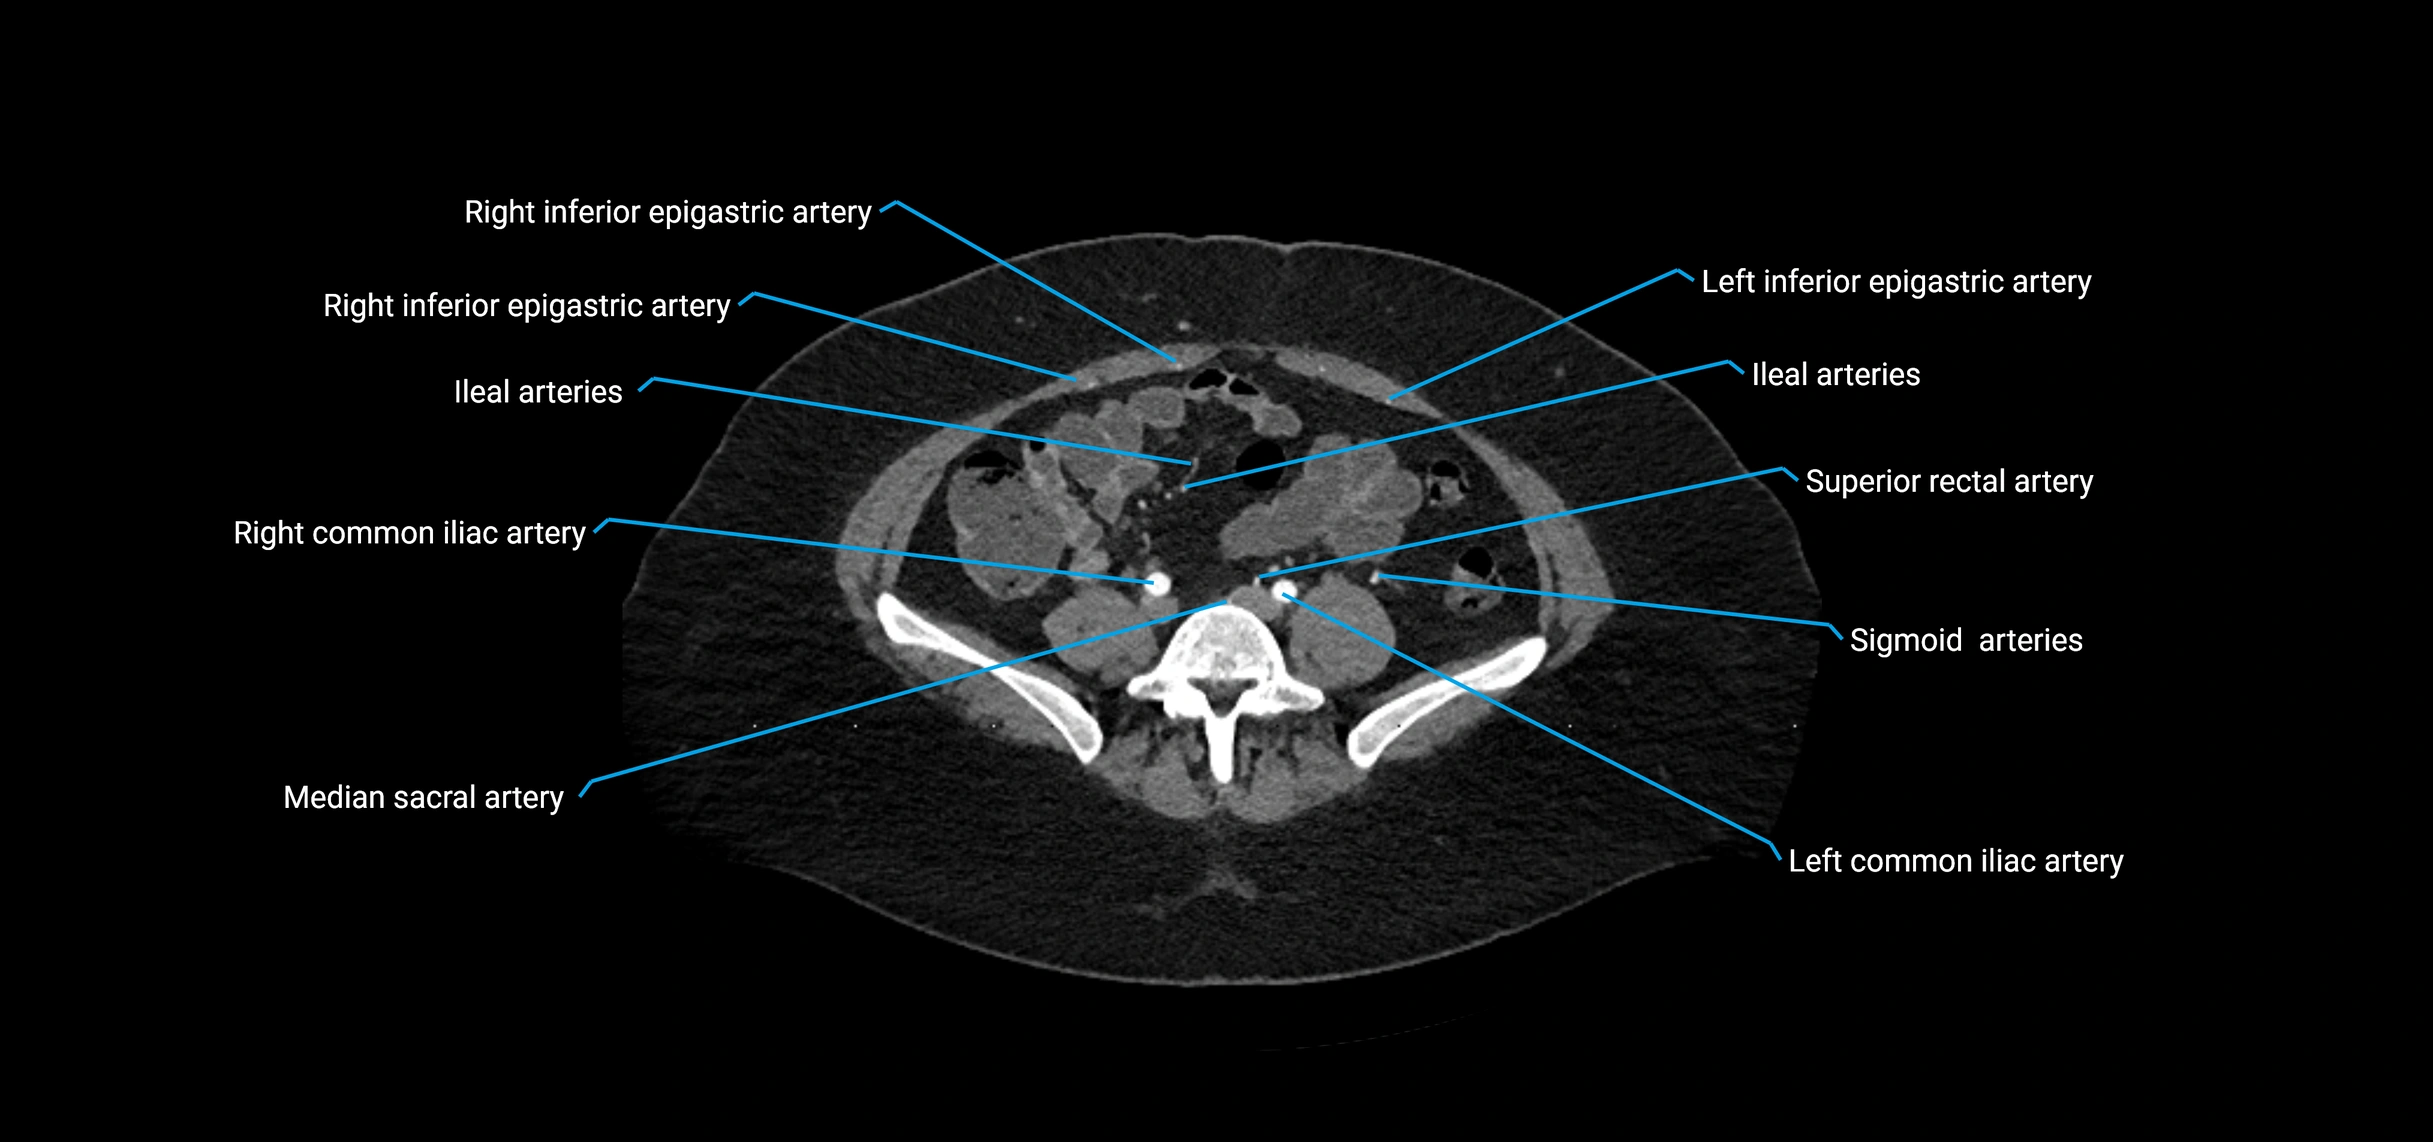

Contrast-enhanced CT (CTA):

• Gold standard for abdominal aortic imaging

• Provides excellent detail of lumen, wall, aneurysm, thrombus, and branch vessels

• Multiplanar and 3D reconstructions help in aneurysm measurement, stent graft planning, and dissection evaluation

• Detects acute rupture, traumatic injury, or occlusion with high sensitivity